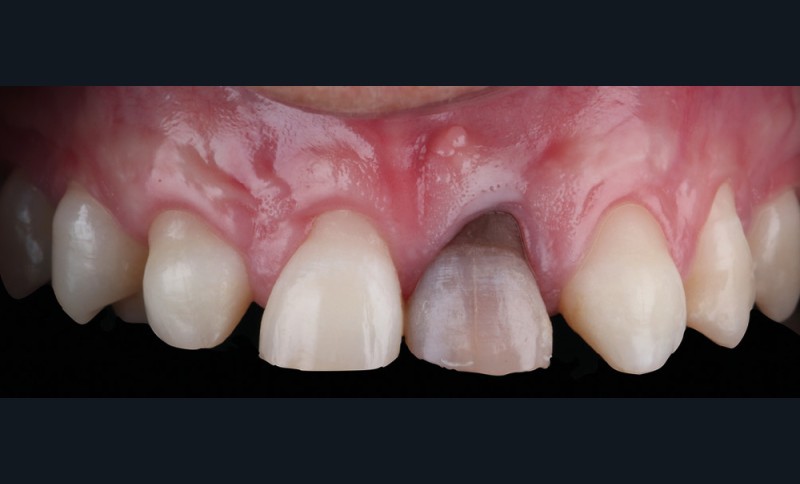

Acte 4 : préparation dentaire et gestion du rose additive (fig. 5 et 6)

À trois mois, les tissus en cours de cicatrisation se stabilisent ; nous passons à la préparation des dents [3].

Au vu des larges plages de cément exposées, nous optons pour une préparation de type couronne sur 53, 11, 21 et 23, afin de privilégier un assemblage prothétique de type scellement. Pour 15, 14, 24 et 25, nous resterons essentiellement dans l’émail et en vestibulaire. Ce choix nous oriente sur une préparation de type facette dont l’assemblage prothétique se fera par collage.

Nous observons que les tissus mous autour de la dent dyschromiée 21 se sont affinés et laissent transparaître le substrat radiculaire [4]. Un épaississement des tissus mous à l’aide d’une greffe de conjonctif s’impose. Dernières retouches également pour la ligne des collets par de petites gingivectomies au bistouri électrique. Des couronnes provisoires, basées sur le nouveau profil d’émergence, sont ensuite posées afin d’obtenir une cicatrisation guidée.